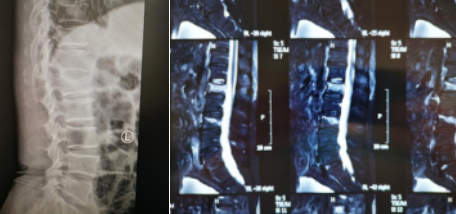

术前设计

手术过程中,孟磊副主任医师在骨科机器人的帮助下,精确定位后,在患者后腰部开了一个直径0.5厘米的小孔,手术器械由此进入,先为患者进行腰椎复位,随后,医生在复位腰椎内注入“骨水泥”,完成治疗。